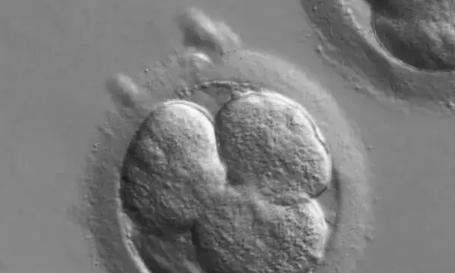

取卵取精后,精卵将在实验室中结合并培养成胚胎。

体外受精与胚胎培养(10,000元 - 20,000元):包括精卵体外受精(常规IVF)、胚胎早期培养、囊胚培养等。若需进行单精子卵胞浆内注射(ICSI,即第二代试管婴儿),会额外增加3,000元 -

6,000元的费用。